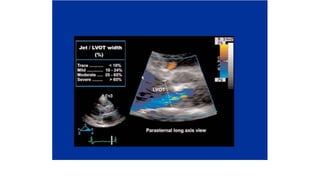

• Transthoracic echocardiography with Doppler colorflow is the most useful tool for the diagnosis of AR.

• The jet width and vena contracta width on Doppler color-flow are used to qualitatively assess the severity of

AR, whereas the regurgitant volume, regurgitant fraction, and regurgitant orifice area are used for the

quantitative assessment.

DIAGNOSTIC CRITERIA • Transthoracicechocardiography with Doppler colorflow is the most useful tool for the diagnosis of AR. • The jet width and vena contracta width on Doppler color-flow are used to qualitatively assess the severity of AR, whereas the regurgitant volume, regurgitant fraction, and regurgitant orifice area are used for the quantitative assessment.